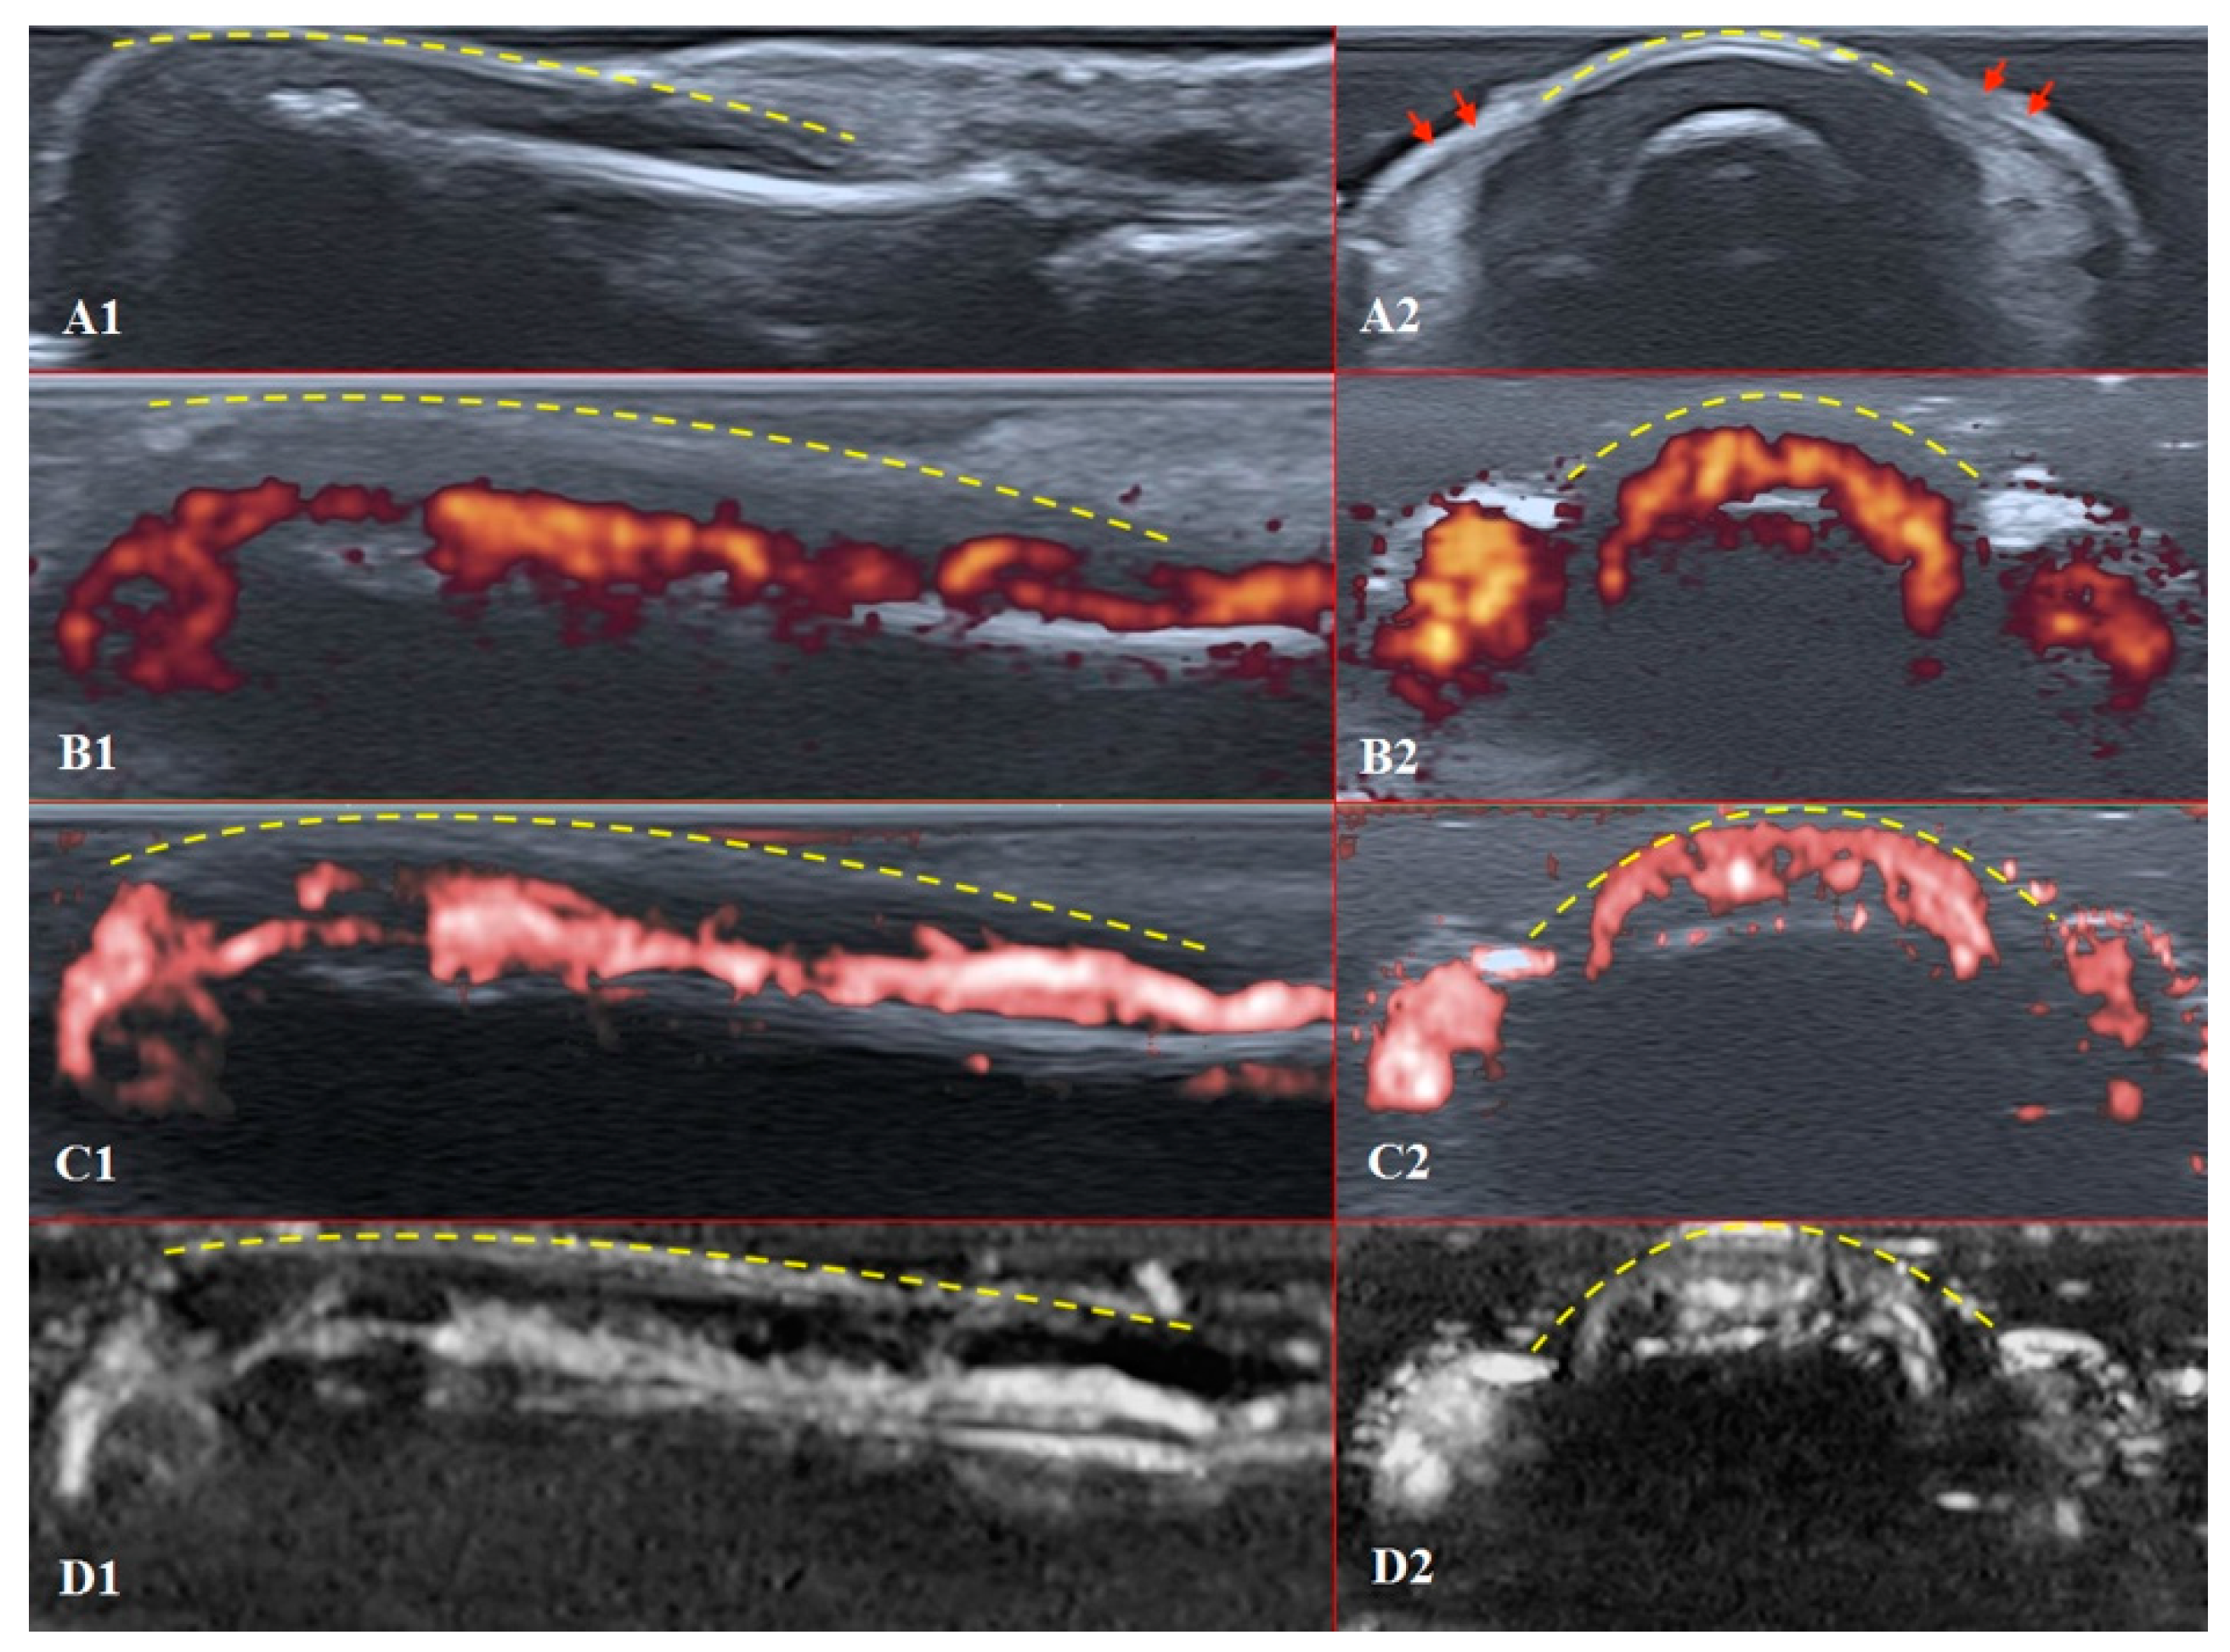

PD and SMI settings have to be standardised for all evaluations. There is an appropriate option to differentiate primary Raynaud’s syndrome from its secondary development by setting the gain. Martinoli et al. suggested increasing the gain maximally and then slowly lowering it until the noise disappears and true signals remain [20]. Rubin offered a converse way to raise the gain manually until the colour box becomes filled with signals and a true flow is distinguished from the background as the next highest signal [21]. The method by Rubin seems to be a quick and comfortable technique to check vascularity in fingertip pulp and nailfold zones (Figure 6 and Figure 7). It takes less time to evaluate vascularity by SMI modes rather than the conventional PD technique due to its higher sensitivity for low flow. Monochrome SMI is a comfortable mode for the evaluation of vasculature and even vascular torsions, as the true flow has more power, and it is easier to separate these dots from the background of random noise artefacts (Figure 4D2).

Figure 6. Sagittal scans of a healthy fingertip with high gain: (A) PD; (B) cSMI; (C) mSMI. The true flow is the highest signal that dissociates from the random noise dots clearly. It is hard to say how much blooming artefact is involved. The transverse dotted line through all images separates the area under the nail close to the fingertip (red dotted line); a gel manicure does not change the quality of the image but longer nails provoke flash artefacts.